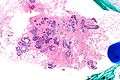

Very low magnification micrograph of atypical ductal hyperplasia (ADH). The piece with ADH was circled by the pathologist with a marker, as it is so small, and sent for an additional opinion. H&E stain. | |

The name of the entity is descriptive of the lesion; ADH is characterized by cellular proliferation (hyperplasia) within one or two breast ducts and (histomorphologic) architectural abnormalities, i.e. the cells are arranged in an abnormal or atypical way.

ADH, cytologically, architecturally and on a molecular basis, is identical to a low-grade ductal carcinoma in situ (DCIS);[4] however, it has a limited extent, i.e. is present in a very small amount (< 2 mm).